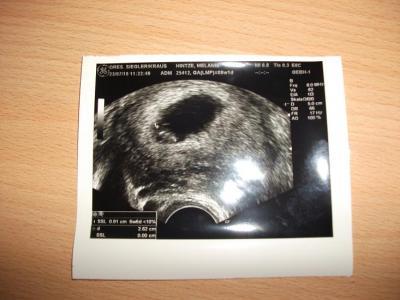

und im us sah man ein süßes kleines krümelchen mit schlagendem herzen,ich bin auf dem stuhl dahingeschmolzen

ich wurde erstmal um eine woche zurück gestuft,bin also heute statt 8+1, erst 7+1,aber damit kann ich auch leben.

und ich bekam noch ein bildchen und das will ich euch natürlich nicht vorenthalten.